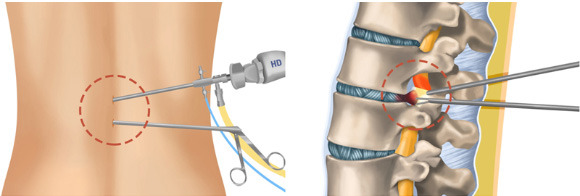

🚀 새 길의 핵심: 비절제·최소침습

② 어떻게 가능해졌나?

- 고해상도 내시경

- 정밀 영상 유도 기술

- 미세 기구 발전

👉 정상 조직은 최대한 보존, 문제 부위만 정확히 치료

🧠 대표적 적용 분야

- 허리디스크

- 척추관협착증

- 만성 요통·좌골신경통

✔ 절개 최소

✔ 출혈 감소

✔ 입원 기간 단축

✔ 고령자도 부담 ↓